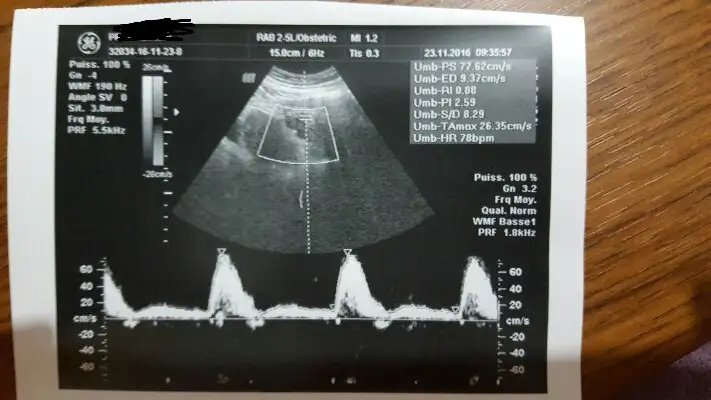

Rahim duvarını besleyen damarlar ,duvar ince olunca kan akımı da az oluyor besleyen damarlarda.. ama yine de akıma bakıldığını yeni duydum , ben duvara bakanı bile bulamadımCanim ultrason ile karindan bakti ve sonra kalp atisi gibi biseyler cikti ekranda. olctu biçti biseyler yapti. sonra rahim damarlarin cok ince dedi. rahim filmi cektirmen lazim dedi. sonra masaya gecince tekrar sordum damar mi duvar mi o zmaan da her ikisi de ince. zaten hamile kalsan da bu sartlarda tutunamaz dedi.

Bana da ilk defa bunu soyleyen oldu canim. doktoru sevdim ama baya. ultrasonu da cok farkli ben vajinal bakar dedim ama karindan bakti. cihaz iyi dedi.Rahim duvarını besleyen damarlar ,duvar ince olunca kan akımı da az oluyor besleyen damarlarda.. ama yine de akıma bakıldığını yeni duydum , ben duvara bakanı bile bulamadım